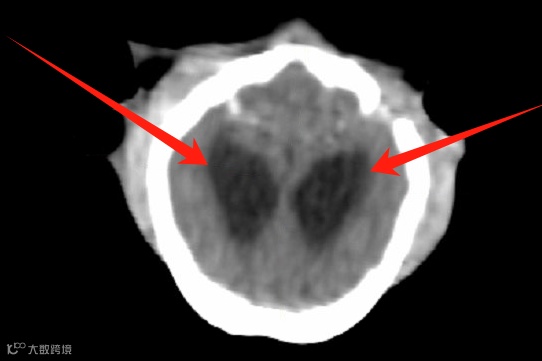

上、下颌联合骨折。